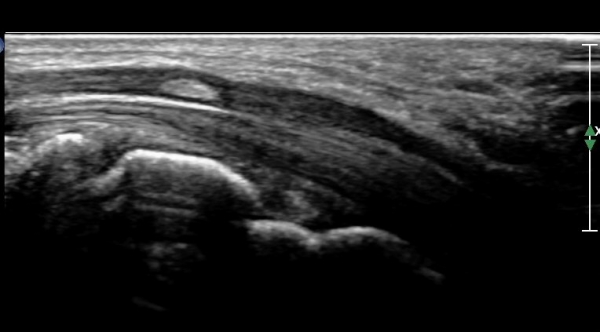

¼Õ¸ñ ºÎÀ§¿¡ Á¤Á߽Űæ Á¾´Ü¸é°Ë»ç»ó Á¤Á߽Ű泻 Ÿ¿øÇüÀÇ °í¿¡ÄÚ Á¾±«°¡ °üÂûµÇ´Âµ¥(»çÁø 3)